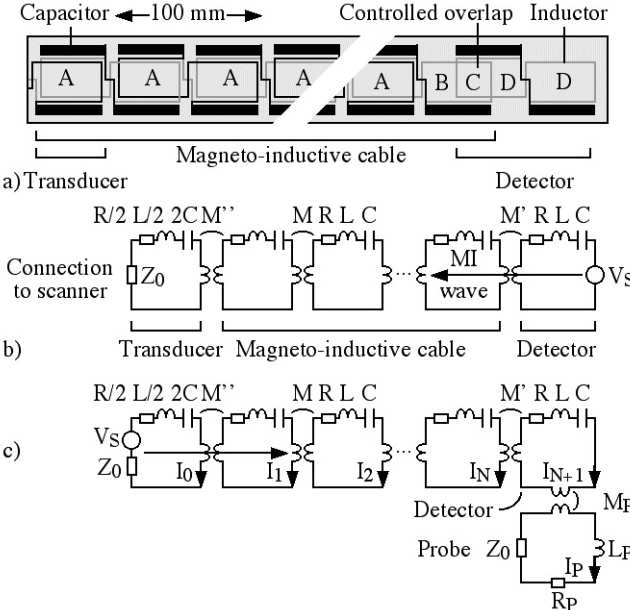

Richard Syms, Ian Young, Marc Rea

We have developed frequency-scaling rules for catheter-based magneto-inductive magnetic resonance imaging detectors, intended for in vivo imaging of the vascular and biliary ductal systems. The design is based on a cascade of magnetically coupled L-C resonators, fabricated as a thin-film circuit and mounted on a catheter. Intrinsic safety is introduced using resonant elements designed to avoid coupling to uniform RF magnetic and electric fields. We have used these rules to demonstrate frequency scaling of developed designs from 1.5 T to 3 T, and carried out mapping of reception patterns and high-resolution 1H imaging in a 3 T clinical scanner.

|

|---|

| CAD layout, PCB, completed catheter and inductive coupling transducer for a magneto-inductive catheter receiver. |

|

|---|

| Frequency response of catheter receivers designed for operation at 1.5T and 3 T. |

|

|---|

| Coronal image of cuboid phantom obtained with an MI catheter receiver, and reception pattern reconstructed from coronal images. |

Richard Syms, Evi Kardoulaki and Ian Young

Simon Taylor-Robinson, Chris Wadsworth and Marc Rea (St Mary’s Hospital)

We have developed a magnetic resonance imaging duodenoscope, by combining non-magnetic endoscope components with a thin-film receiver based on a magneto-inductive waveguide. The waveguide elements consist of figure-of-eight shaped inductors formed on either side of a flexible substrate and parallel plate capacitors that use the substrate as a dielectric. Operation has been simulated using equivalent circuit models and by computation of sensitivity patterns. Circuits have been fabricated for operation at 127.7 MHz by double-sided patterning of copper-clad Kapton and assembled onto non-magnetic flexible endoscope insertion tubes. Operation has been verified by bench testing and by 1H MRI at 3T using phantoms. The receiver can form a segmented coaxial image along the length of the endoscope, even when bent, and shows a signal-to-noise-ratio advantage over a surface array coil up to three times the tube diameter at the tip. Initial immersion imaging experiments have been carried out and confirm an encouraging lack of sensitivity to RF heating.

|

|---|

| Electrical layout of thin film PCB (a), and equivalent circuit models for imaging (b) and electrical testing (c). |

|

|---|

| Arrangement for magnetic resonance imaging with cuboid phantoms (a), body coil image showing effective decoupling (b) and metamaterial coil image, showing segmented field of view (c). |